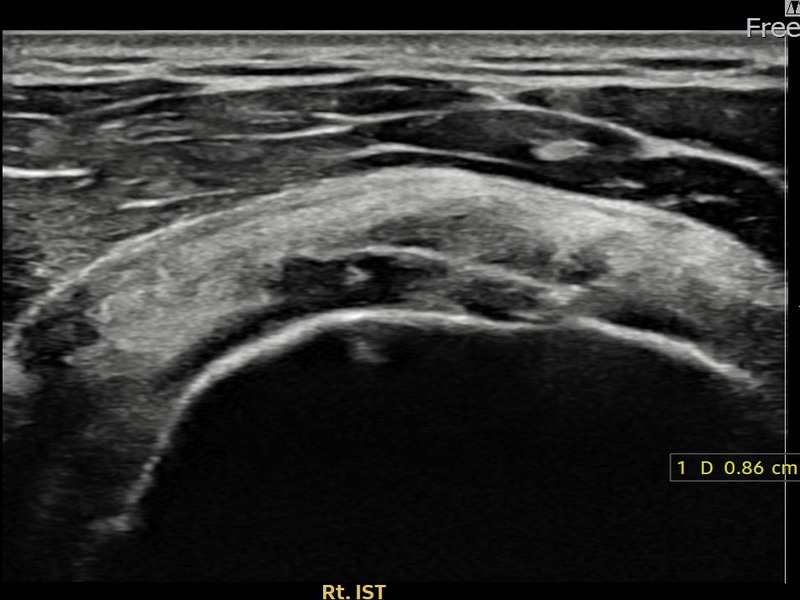

김ㅇㅇ님 · 우측 극하근건 관절면측 부분파열

우측 어깨 후방 통증과 팔을 바깥으로 돌릴 때 통증이 심해 내원하셨습니다. 초음파 검사에서 극하근건 관절면측 부분파열이 확인되었으며, 어깨인대 축소봉합술 후 힘줄 구조적 안정화가 이루어졌습니다.

김ㅇㅇ님 · 우측 극하근건 부착부 부분파열

우측 어깨 후방 통증과 외회전 시 심한 통증으로 내원하셨습니다. 초음파 검사에서 극하근건 부착부 부분파열이 확인되었으며, 어깨인대 축소봉합술 후 부착부 힘줄 연속성이 회복되었습니다.